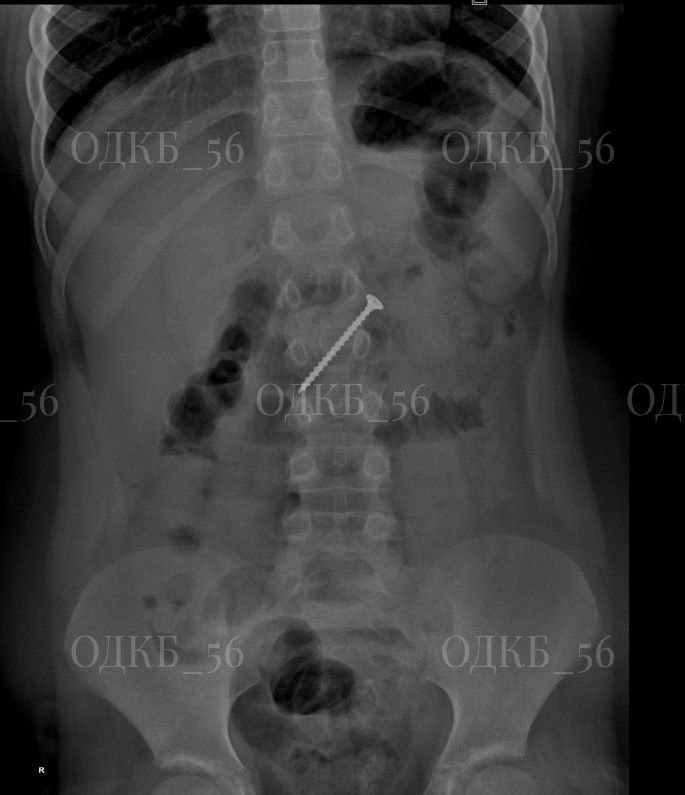

Рентген подтвердил, что саморез находился в желудке, но к моменту госпитализации уже переместился в двенадцатиперстную кишку, создавая угрозу кишечной непроходимости и перфорации.

Врачи срочно провели эндоскопию и успешно извлекли инородное тело. Состояние ребенка стабильное.